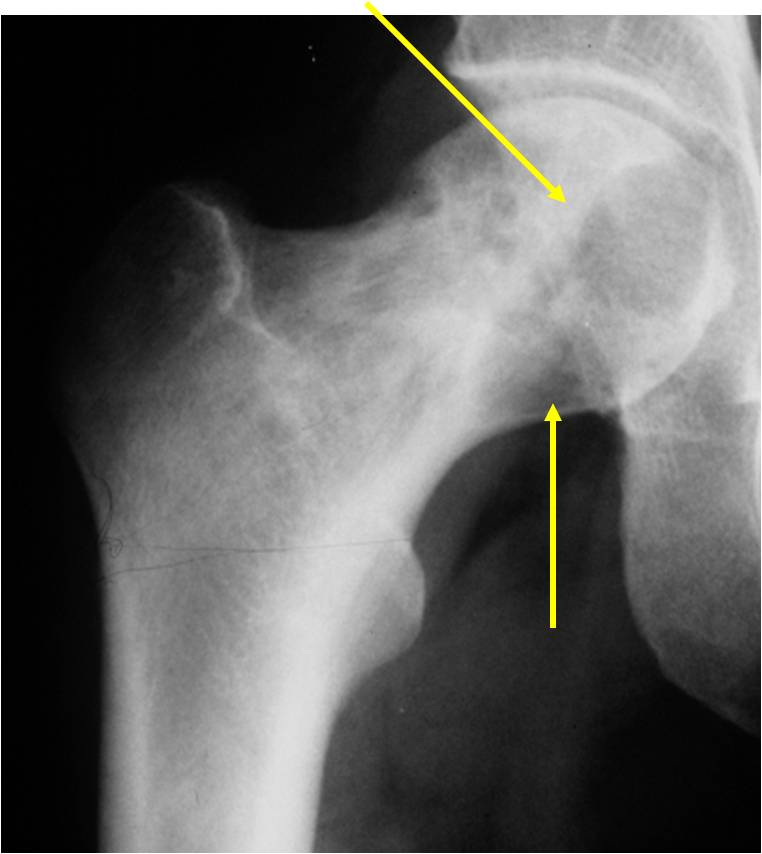

Radiographic Presentation

- Usually osteolytic, expansile lesion

- May be focally calcified

- Often a sharp interface between tumor and surrounding bone

- Sclerotic rim is uncommon

- Overlying cortex is usually thin, but intact